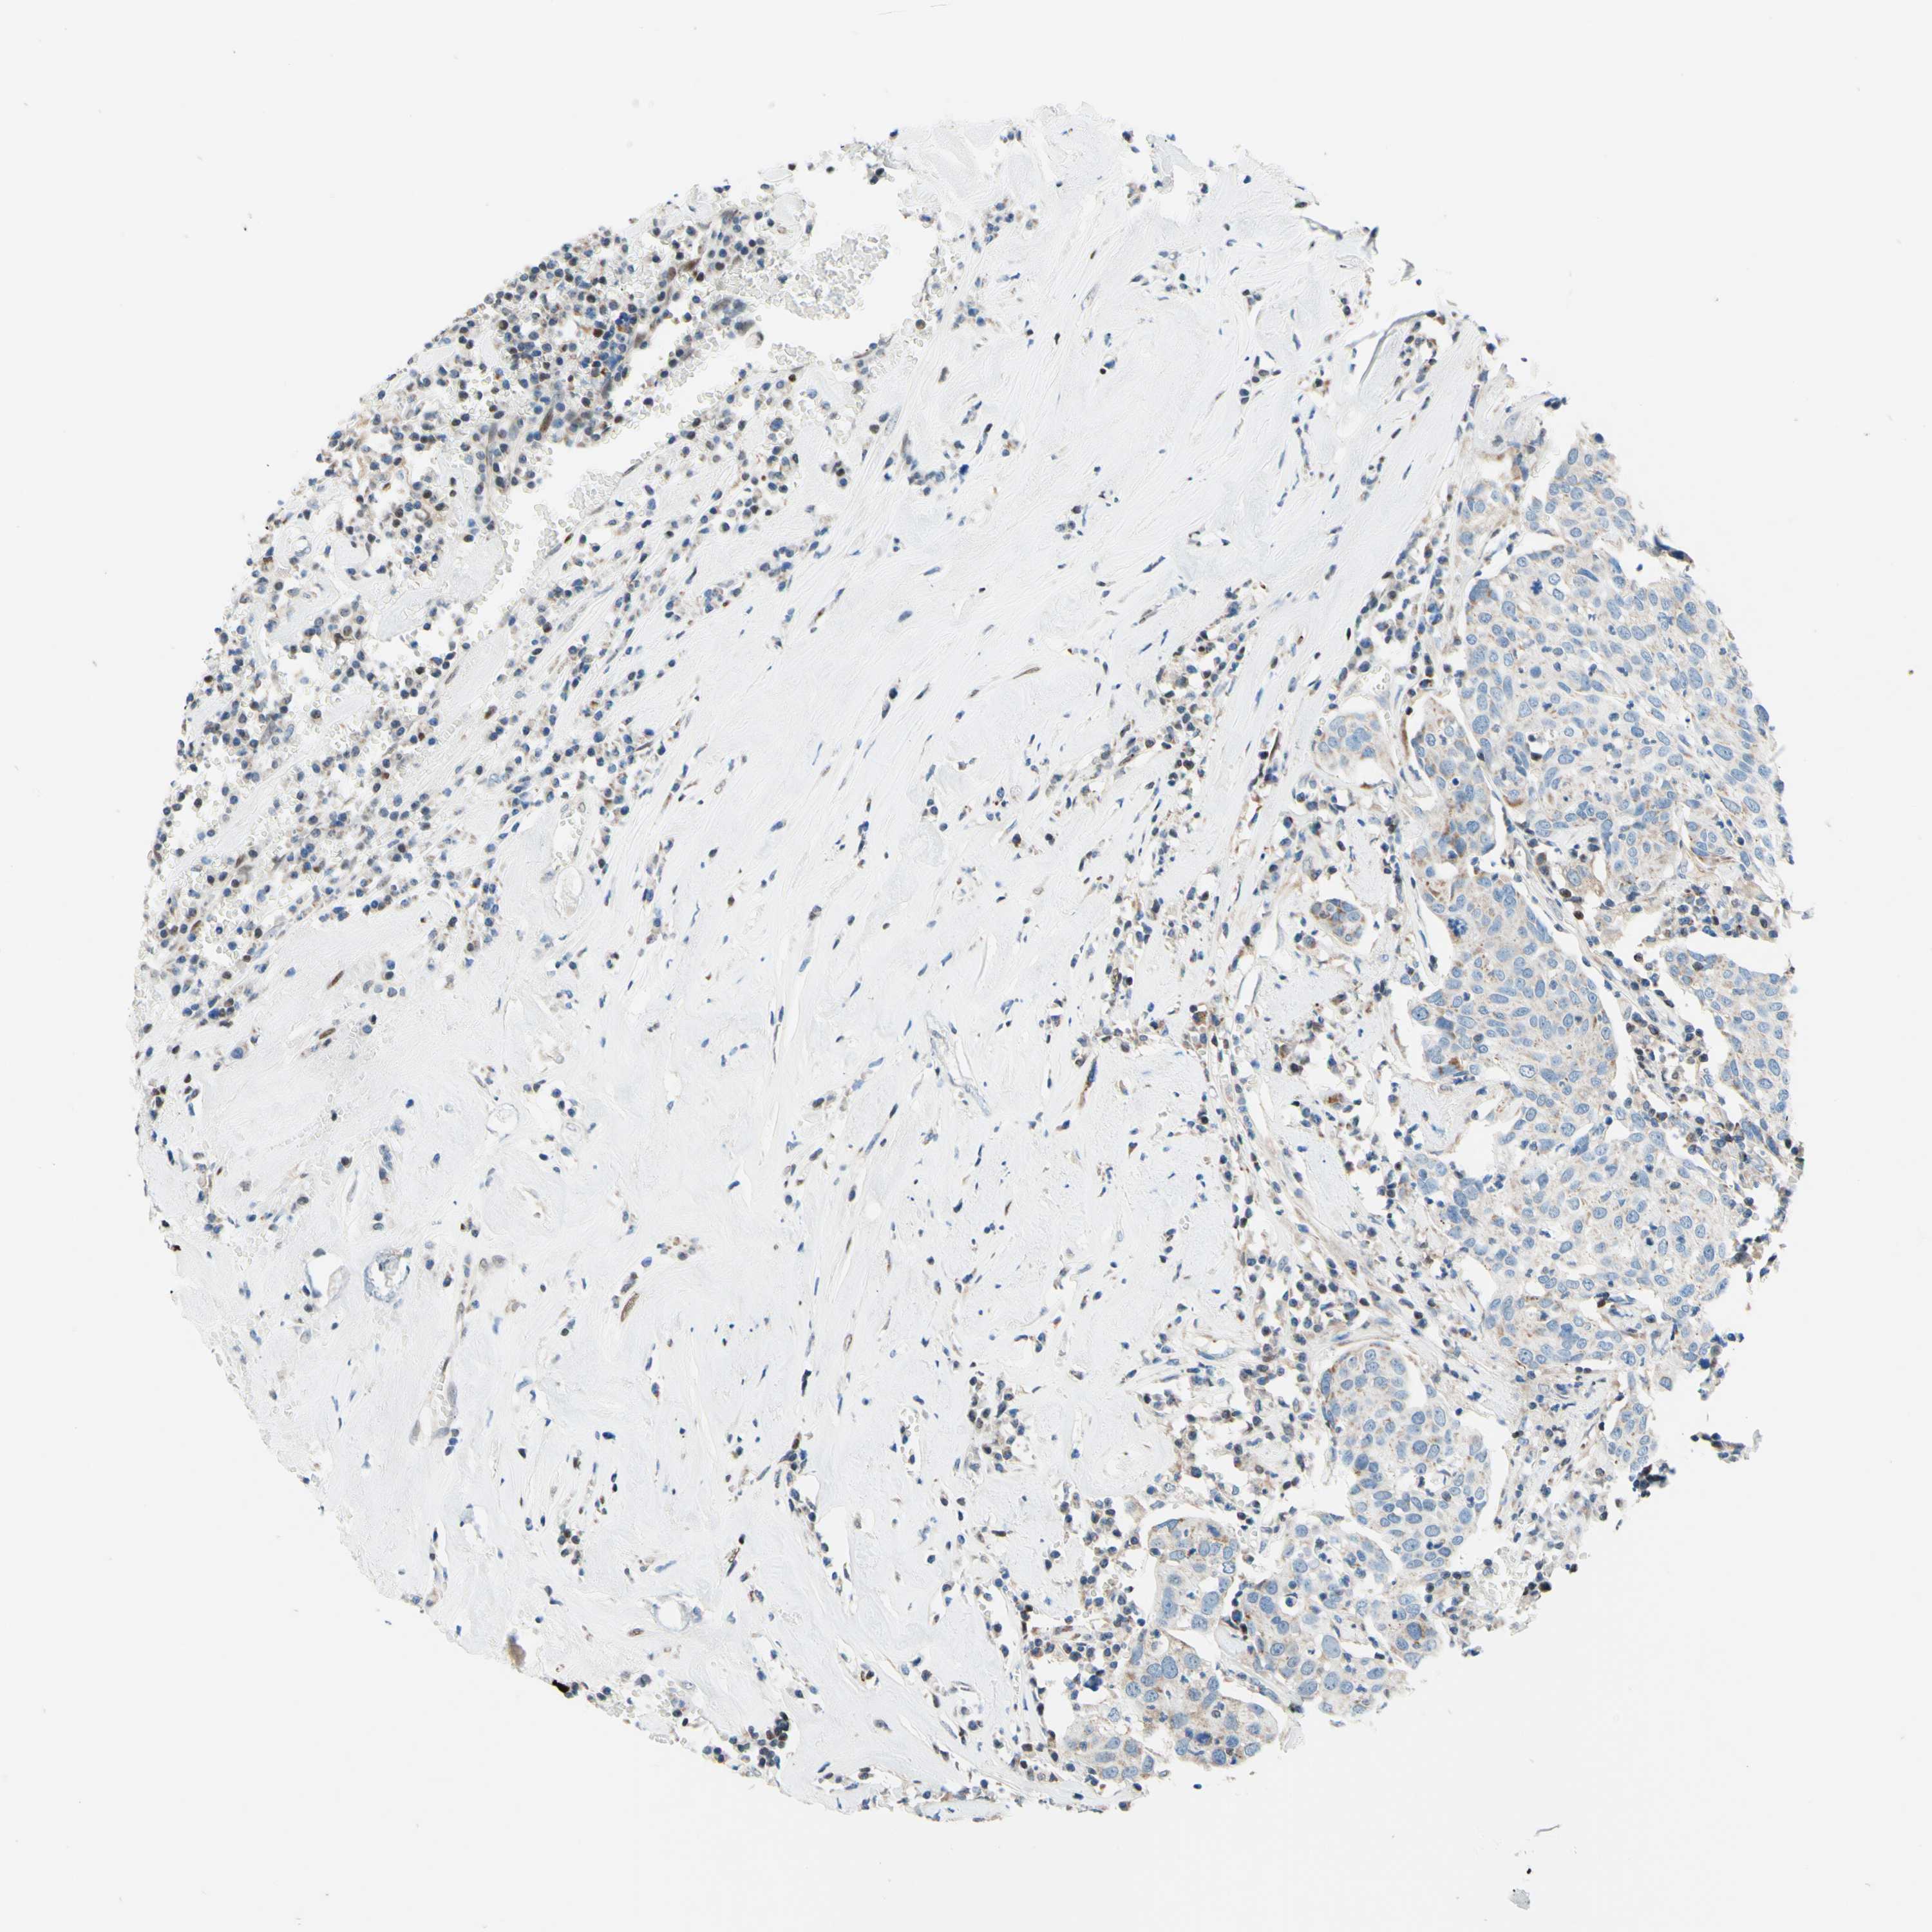

HEAD AND NECK CANCER - Protein expressioni

A mouse-over function shows sample information and annotation data. Click on an image to view it in a full screen mode. Samples can be filtered based on level of antibody staining by selecting one or several of the following categories: high, medium, low and not detected. The assay and annotation is described here.

Antibody stainingi

Antibody staining in the annotated cell types in the current human tissue is reported as not detected, low, medium, or high, based on conventional immunohistochemistry profiling in selected tissues. This score is based on the combination of the staining intensity and fraction of stained cells.

Each image is clickable and will lead to virtual microscopy that enables deeper exploration of all samples and also displays staining intensity scores, fraction scores and subcellular localization as well as patient and tissue information for each sample.

Antibody HPA048677

Antibody HPA056480

Antibody CAB011574

Staining

High

Medium

Low

Not detected

Intensity

Strong

Moderate

Weak

Negative

Quantity

>75%

75%-25%

<25%

None

Location

Nuclear

Cytoplasmic/membranous

Cytoplasmic/membranous,nuclear

Adenocarcinoma, NOS

Squamous cell carcinoma, NOS

Squamous cell carcinoma, metastatic, NOS

Adenoma, NOS